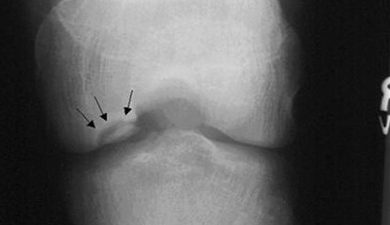

Хвороба Кеніга (розсікаючий остеохондрит колінного суглоба) – досить рідкісне захворювання, при якому розвивається обмежений остеонекроз ділянки субхондральної кістки,